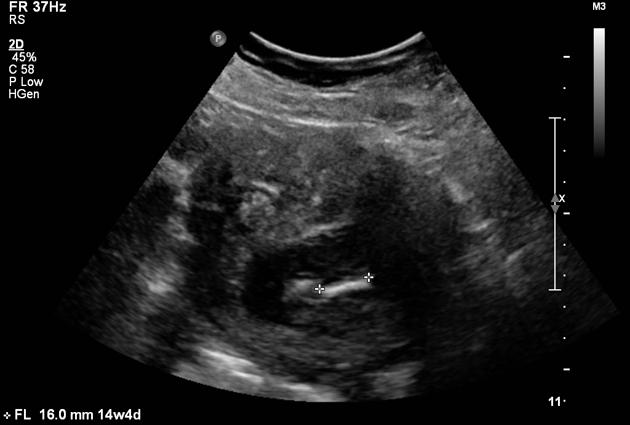

Fetal megacystis is characterised by an abnormally enlarged bladder visible on an ultrasound during pregnancy. It’s most often detected in the first or early second trimester, when the baby’s bladder can be visualised easily. Normally, the fetal bladder fills and empties regularly, a sign that the baby’s urinary system is working well.

In megacystis, the bladder remains persistently enlarged, often measuring more than 7 mm in length before 14 weeks of gestation. This typically suggests that urine is being produced but not emptied efficiently, indicating a possible issue in the lower urinary tract.